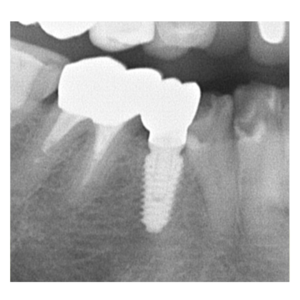

インプラント治療の症例

インプラント治療の症例です。

歯がないのが気になる |

58歳 女性 |

4ヶ月 |

¥350,000(税別) |

腫れ・痛み・神経損傷・インプラント周囲炎・骨吸収 など |